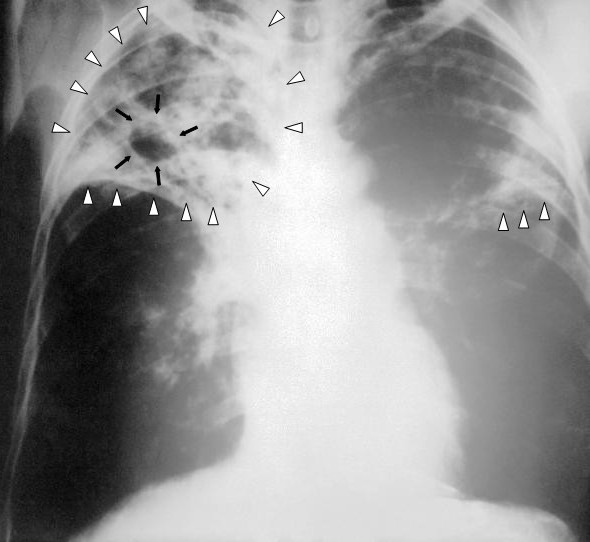

Life cycle of malaria.NIH via <a href="http://commons.wikimedia.org/wiki/File:MalariacycleBig.jpg">Wikimedia Commons</a>.